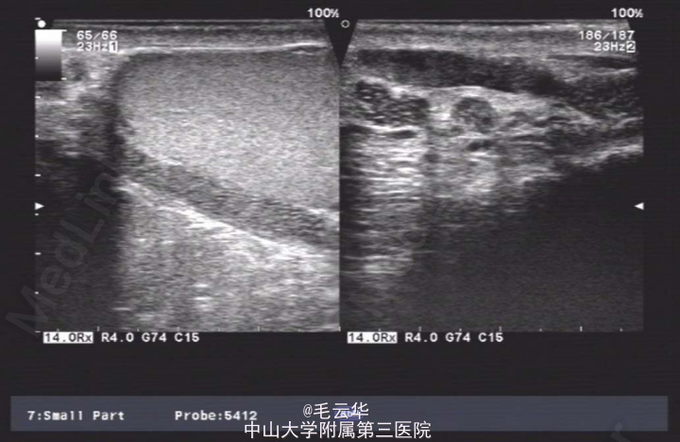

双肾区无红肿、隆起,无叩痛,双侧肋脊点、肋腰点无压痛。腹平软,双侧上中输尿管点无压痛,膀胱区无压痛。双侧腹股沟区未触及肿物,尿道外口未见异常,阴囊无水肿,双睾丸可触及,肛周皮肤无红肿。盆腔MR提示:双侧精囊腺体积缩小(未见片)。彩超提示:右侧输精管、精囊缺如可能;双侧睾丸偏大,附睾小管扩张;前列腺囊肿。精液常规提示精液量少,离心后无精子。

入院诊断:无精症查因。 入院完善术前相关检查,射精管切开+输精管探查术。麻醉成功后,取截石位,常规消毒铺巾,连接好4.5/6.5F输尿管硬镜和监视系统。经尿道进镜入膀胱,见双侧输尿管开口裂隙状,膀胱内未见异常。尿道未见明显异常,精阜稍隆起。镜下未找到双侧射精管开口,硬膜外导管引导进镜入前列腺小囊,见囊腔狭小,囊壁炎性增厚,囊内未见射精管开口,考虑射精管口梗阻,遂换用电切镜,切除部分精阜,切开双侧射精管口,再用硬膜外导管引导输尿管硬镜入射精管,进入困难,结合病史及影像学检查,提示射精管发育不良并梗阻。作双侧阴囊切口,逐层切开,游离出睾丸和精索,探查双侧输精管,见左侧输精管呈纤维条索状,未见管腔结构,右侧未见输精管,考虑为先天缺如,遂行双侧睾丸活检,术野予以止血,逐层缝合切口,术毕。手术过程顺利,麻醉效果满意,术中无出血,术后安返病房。